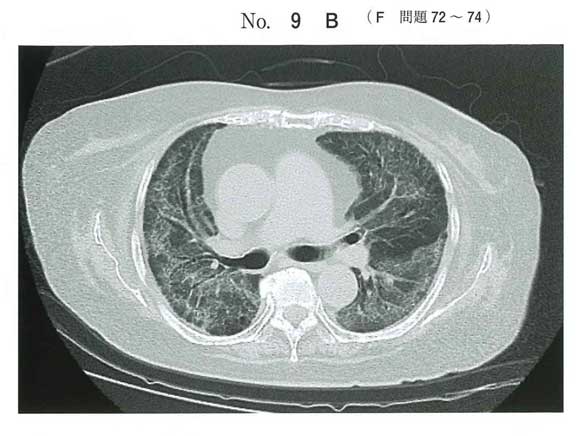

PCP

β-D-グルカン高値→真菌→グロコット染色

ステロイド使うときはニューモシスチス注意ですな